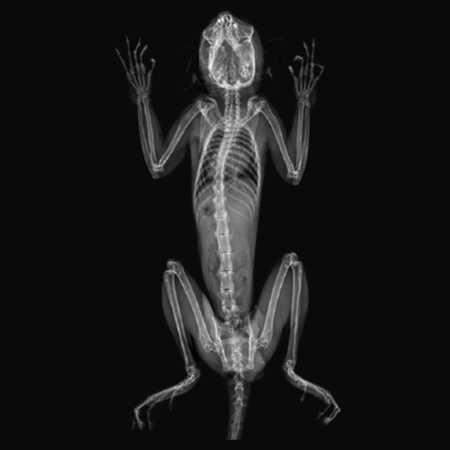

X-Ray Attenuation Image - Rat. Image Credit: Scintica Instrumentation Inc